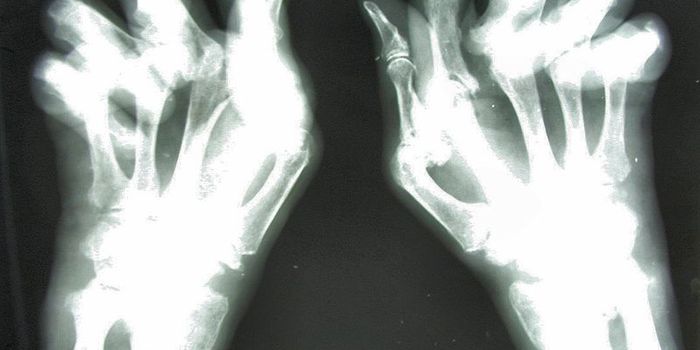

FEB 02, 2024Genetics & GenomicsMillions of people have autoimmune diseases, such as multiple sclerosis or rheumatoid arthritis but it's estim ...

JUN 15, 2019Cell & Molecular BiologyIn RA, cells of the immune system mistakenly attack the joints, and cause the painful inflammation that is a hallmark of ...

SEP 26, 2022ImmunologyResearchers have found that a protein called sulfatase-2 may play a significant role in the tissue damage caused by rheu ...

DEC 02, 2024Genetics & GenomicsA new study reported in Nutrients has identified some of the potential food triggers of arthritis, while an unrelated st ...